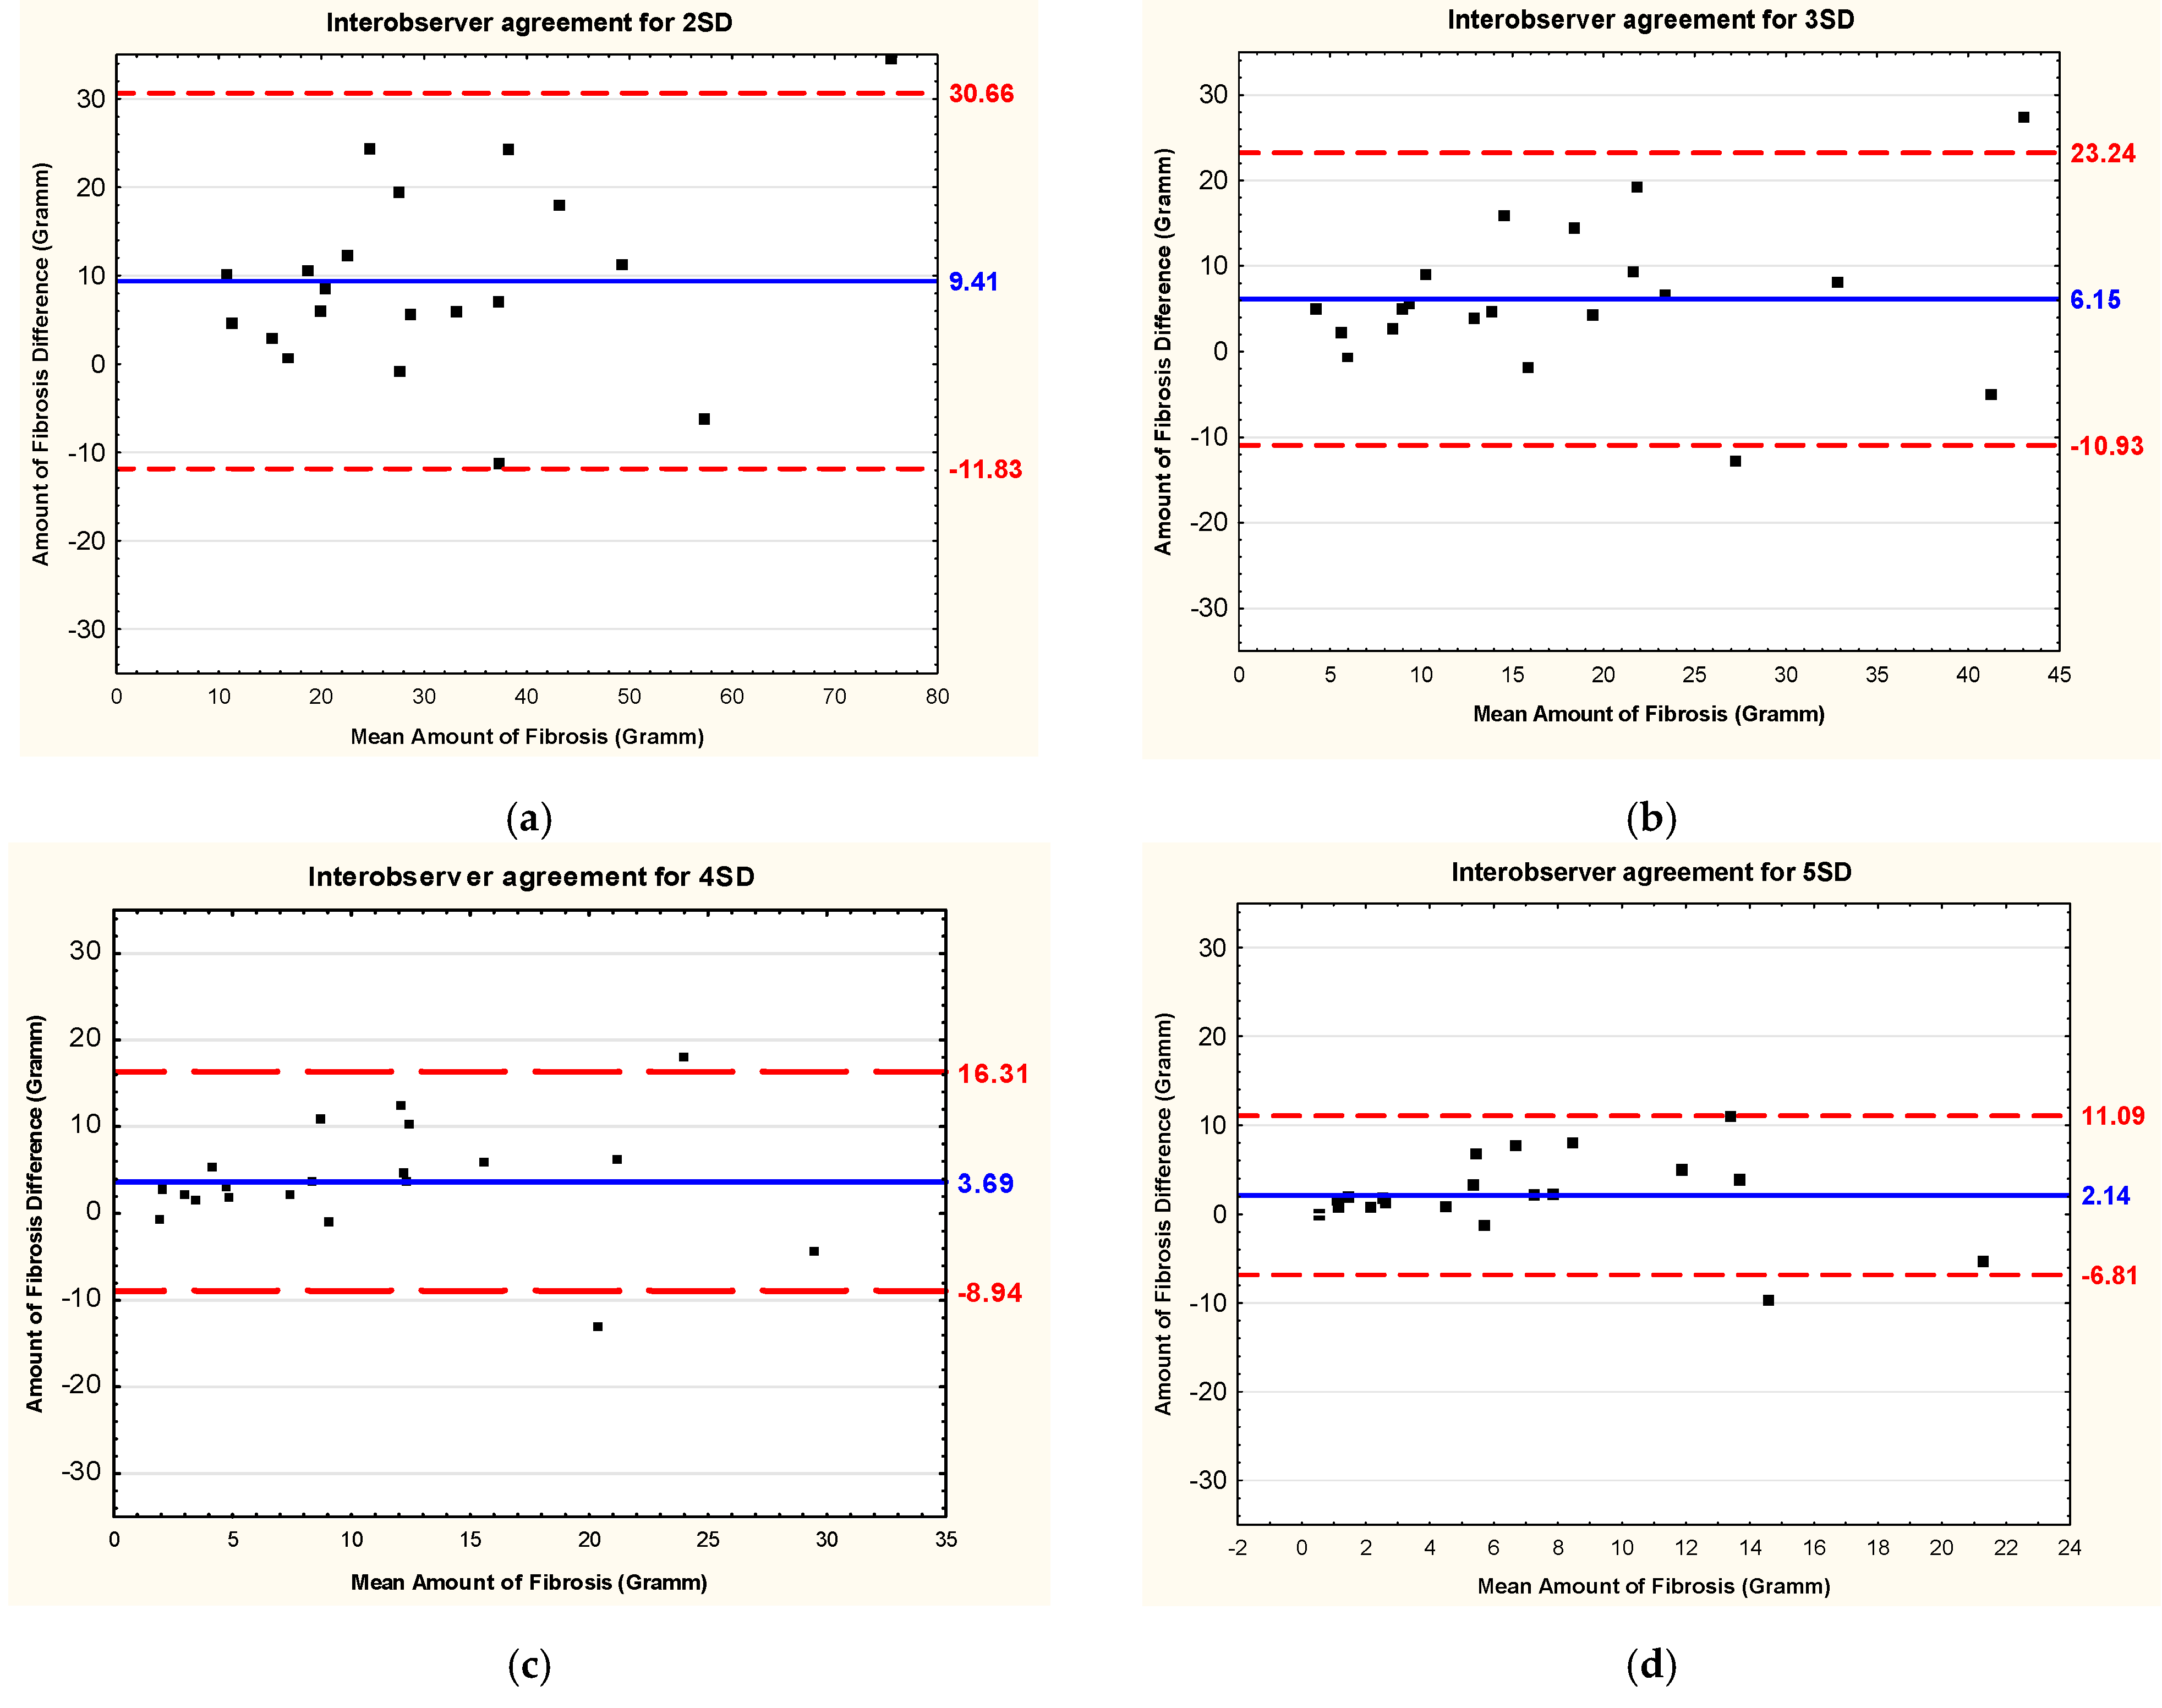

3.3. Intraobserver and Interobserver Reliability and Reproducibility